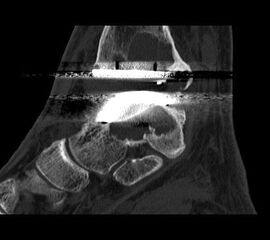

• Optional MRT mit Kontrastmittel zur Beurteilung der Durchblutungssituation des Knochens und bei Verdacht auf Osteonekrosen (Stäbler 2012).

• Optional CT; insbesondere bei ausgedehnten Knochendestruktionen.

• Prothesenplanung anhand von Röntgenschablonen (Abb. 1 und 2).